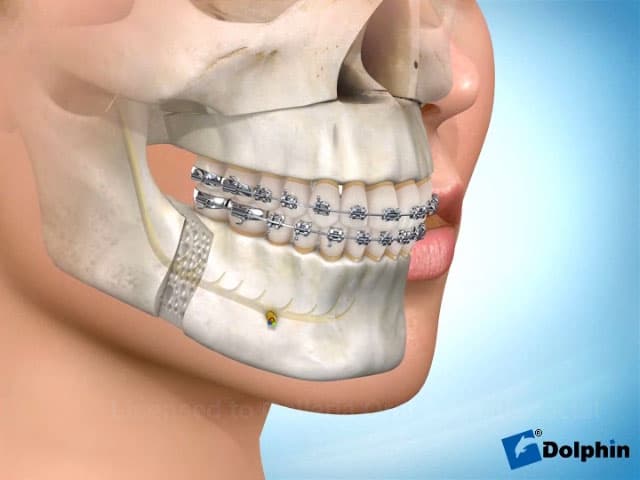

Corrective Jaw Surgery

Computer-planned orthognathic surgery to correct jaw misalignment, restore bite function, and achieve facial harmony. Dr. Antipov treats underbites (Class III malocclusion), overbites (Class II malocclusion), open bites, crossbites, facial asymmetry, and obstructive sleep apnea. Procedures include Le Fort I osteotomy (single-piece and 3-piece), bilateral sagittal split osteotomy (BSSO), genioplasty (chin repositioning), maxillomandibular advancement, and double jaw surgery. Every case uses 3D virtual surgical planning for millimeter-precise results.